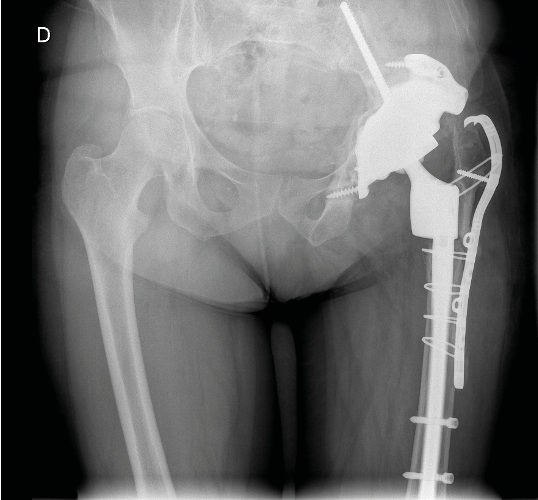

Case report n°2 (Figure 2)

PPF at the cementless pivot (Vancouver B2) after acetabulum-only revision

Femur-only revision: cementless monoblock long stem Locking stem, fracture repair with cerclage wiring.